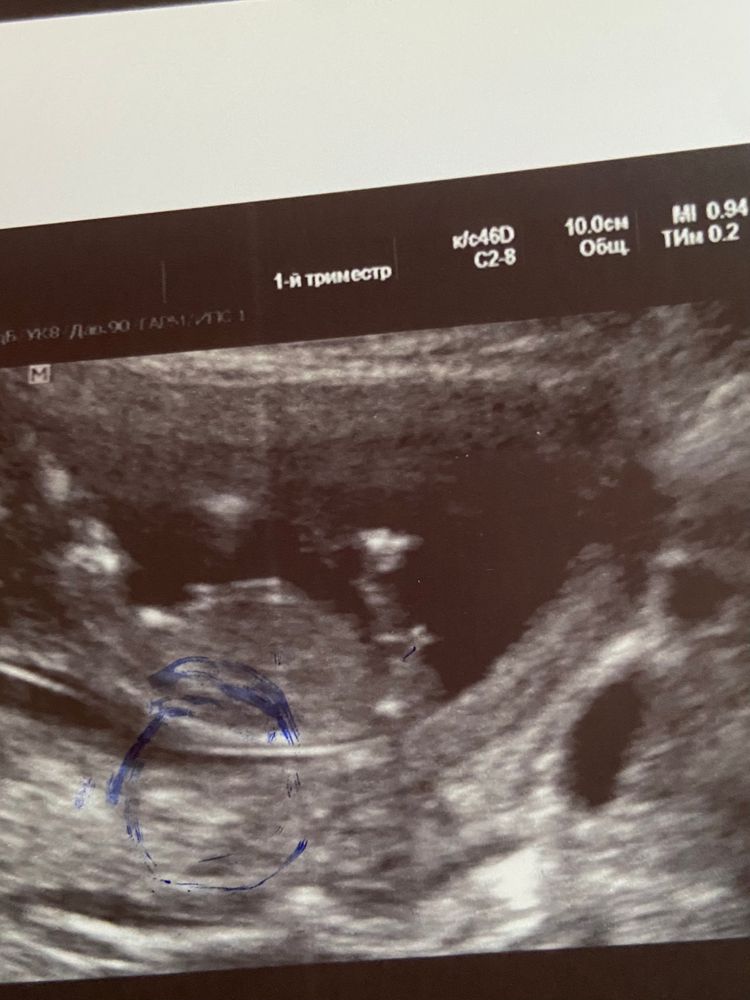

Пол малыша

Пока не подтвердят мне пол, по узи,не успокоюсь 😂 вот нашла узи старшей девочки(где красным обведен), бугорки под разным углом, что у нее, что сегодня делала узи, очень большая надежда, что мальчик🥺

mamadi, неее девочку сразу видно, у нас прямой был бугорок, а тут к верху так что пацан 100%

Ну, да, похоже на мальчика, если это половой бугорок)) Пускай сбывается!